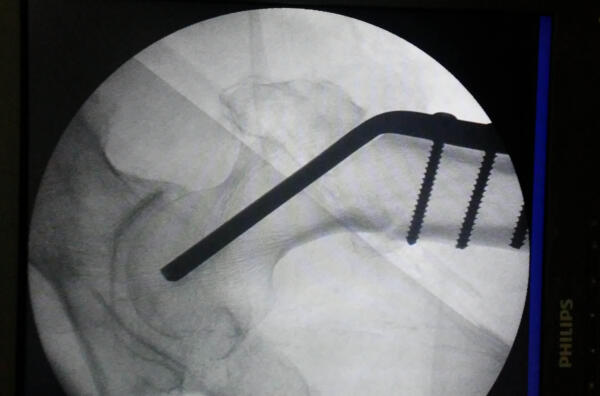

Una cirugía de cadera puede demandar hasta 7 tornillos corticales de 4.5 milímetros. Foto cortesía del entrevistado.

Para esa fijación se usan tornillos, placas, clavos, sistemas de compresión y otros dispositivos de osteosíntesis. Entre ellos están los tornillos corticales de 4.5 milímetros, pensados para hueso cortical denso y para grandes fragmentos, con medidas y usos ampliamente estandarizados en los sistemas de trauma. También existen los tornillos esponjosos, diseñados para el hueso menos denso: presentan una rosca más gruesa y separada, lo que favorece el anclaje en la esponjosa ósea.

En el primer trimestre del año, las fracturas de cadera atendidas en Sancti Spíritus se fijaron con este recurso, con resultados similares a los obtenidos con tornillos importados.

En el primer trimestre del año, las fracturas de cadera atendidas en Sancti Spíritus se fijaron con este recurso. Foto cortesía del entrevistado.